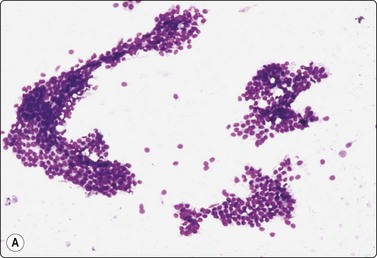

image image

Fig. 7.2 Non-neoplastic glandular breast tissue and low-grade duct carcinoma

Low-power view; (A) Bimodal population of epithelial sheets and single bipolar nuclei of non-neoplastic glandular breast tissue; (B) Single population of epithelial cells in low-grade carcinoma (MGG, LP).